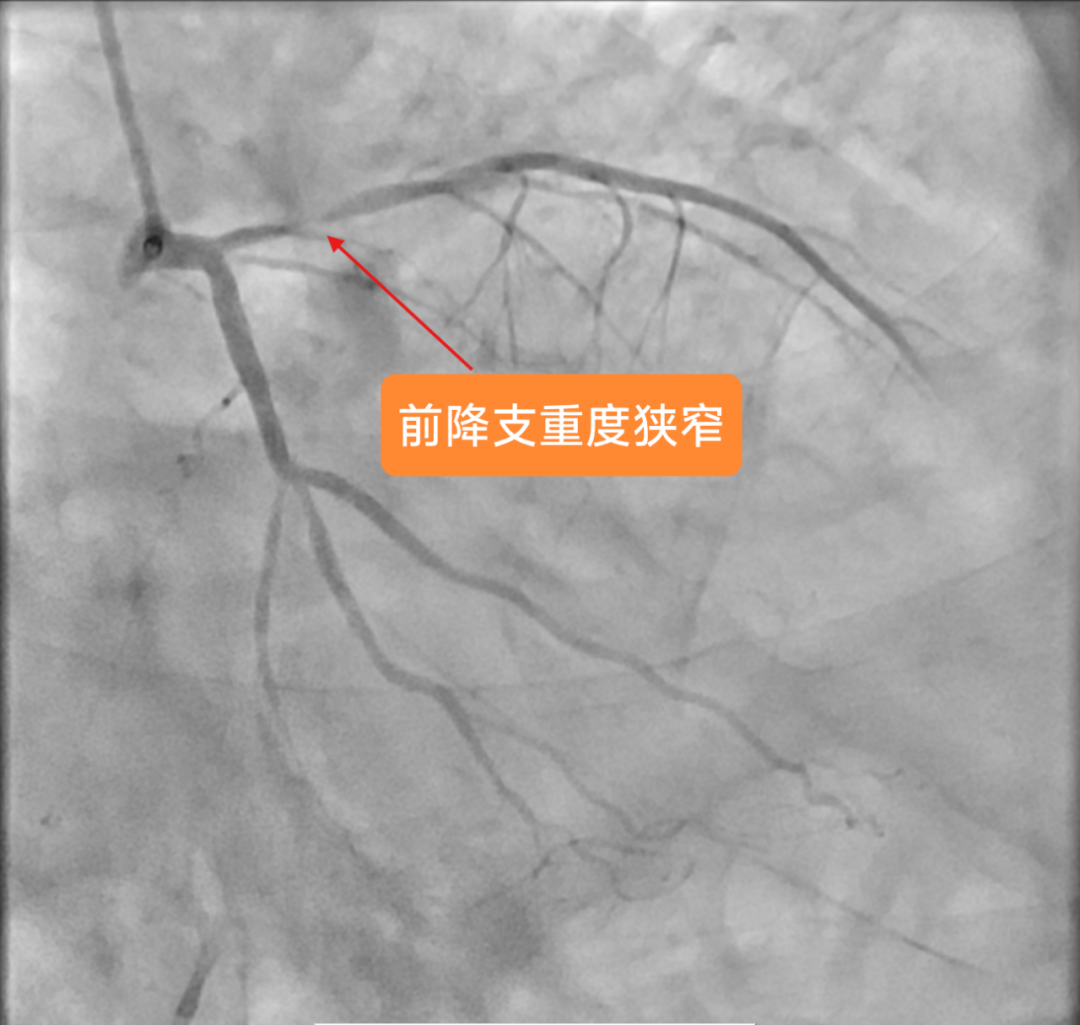

2025年3月4日手术当天,医生穿刺患者右桡动脉进行造影时,一场危象毫无征兆地出现:患者前降支血管近段狭窄达99%,血管近乎完全闭塞。这意味着心脏随时面临因严重缺血而停跳的危险,大脑也承受着巨大且不可逆的缺血性损伤风险,情况刻不容缓,必须立即进行紧急手术,这是挽救患者生命的关键。

冠脉造影显示患者前降支血管重度狭窄